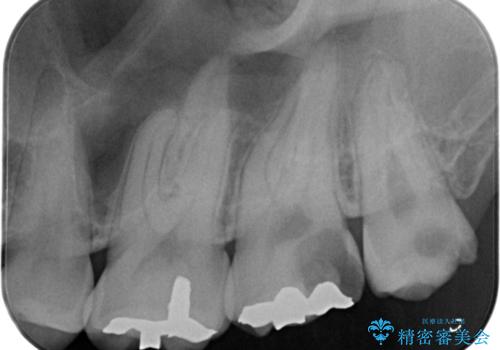

- 奥歯が欠けてしみるとのことで来院された患者様です。

かなり大きな虫歯であることと、清掃不良により歯全体が脱灰していたため、クラウンでの修復処置を行います。

奥に生えている親知らずも清掃不良であったため、今回治療する歯の清掃性を高めるために抜歯を行います。

かなり大きな虫歯でしたが症状も出ず、根管治療もせずに終えることができました。